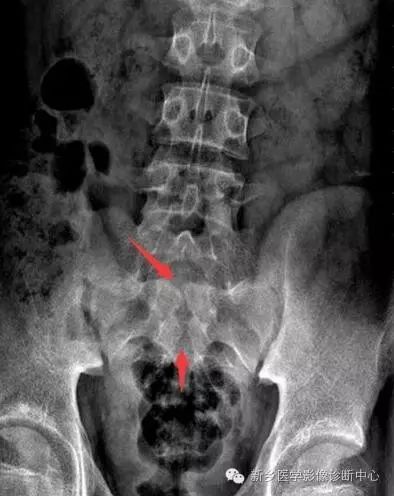

图. 男性,14岁,X线下典型的椎体扇贝样改变